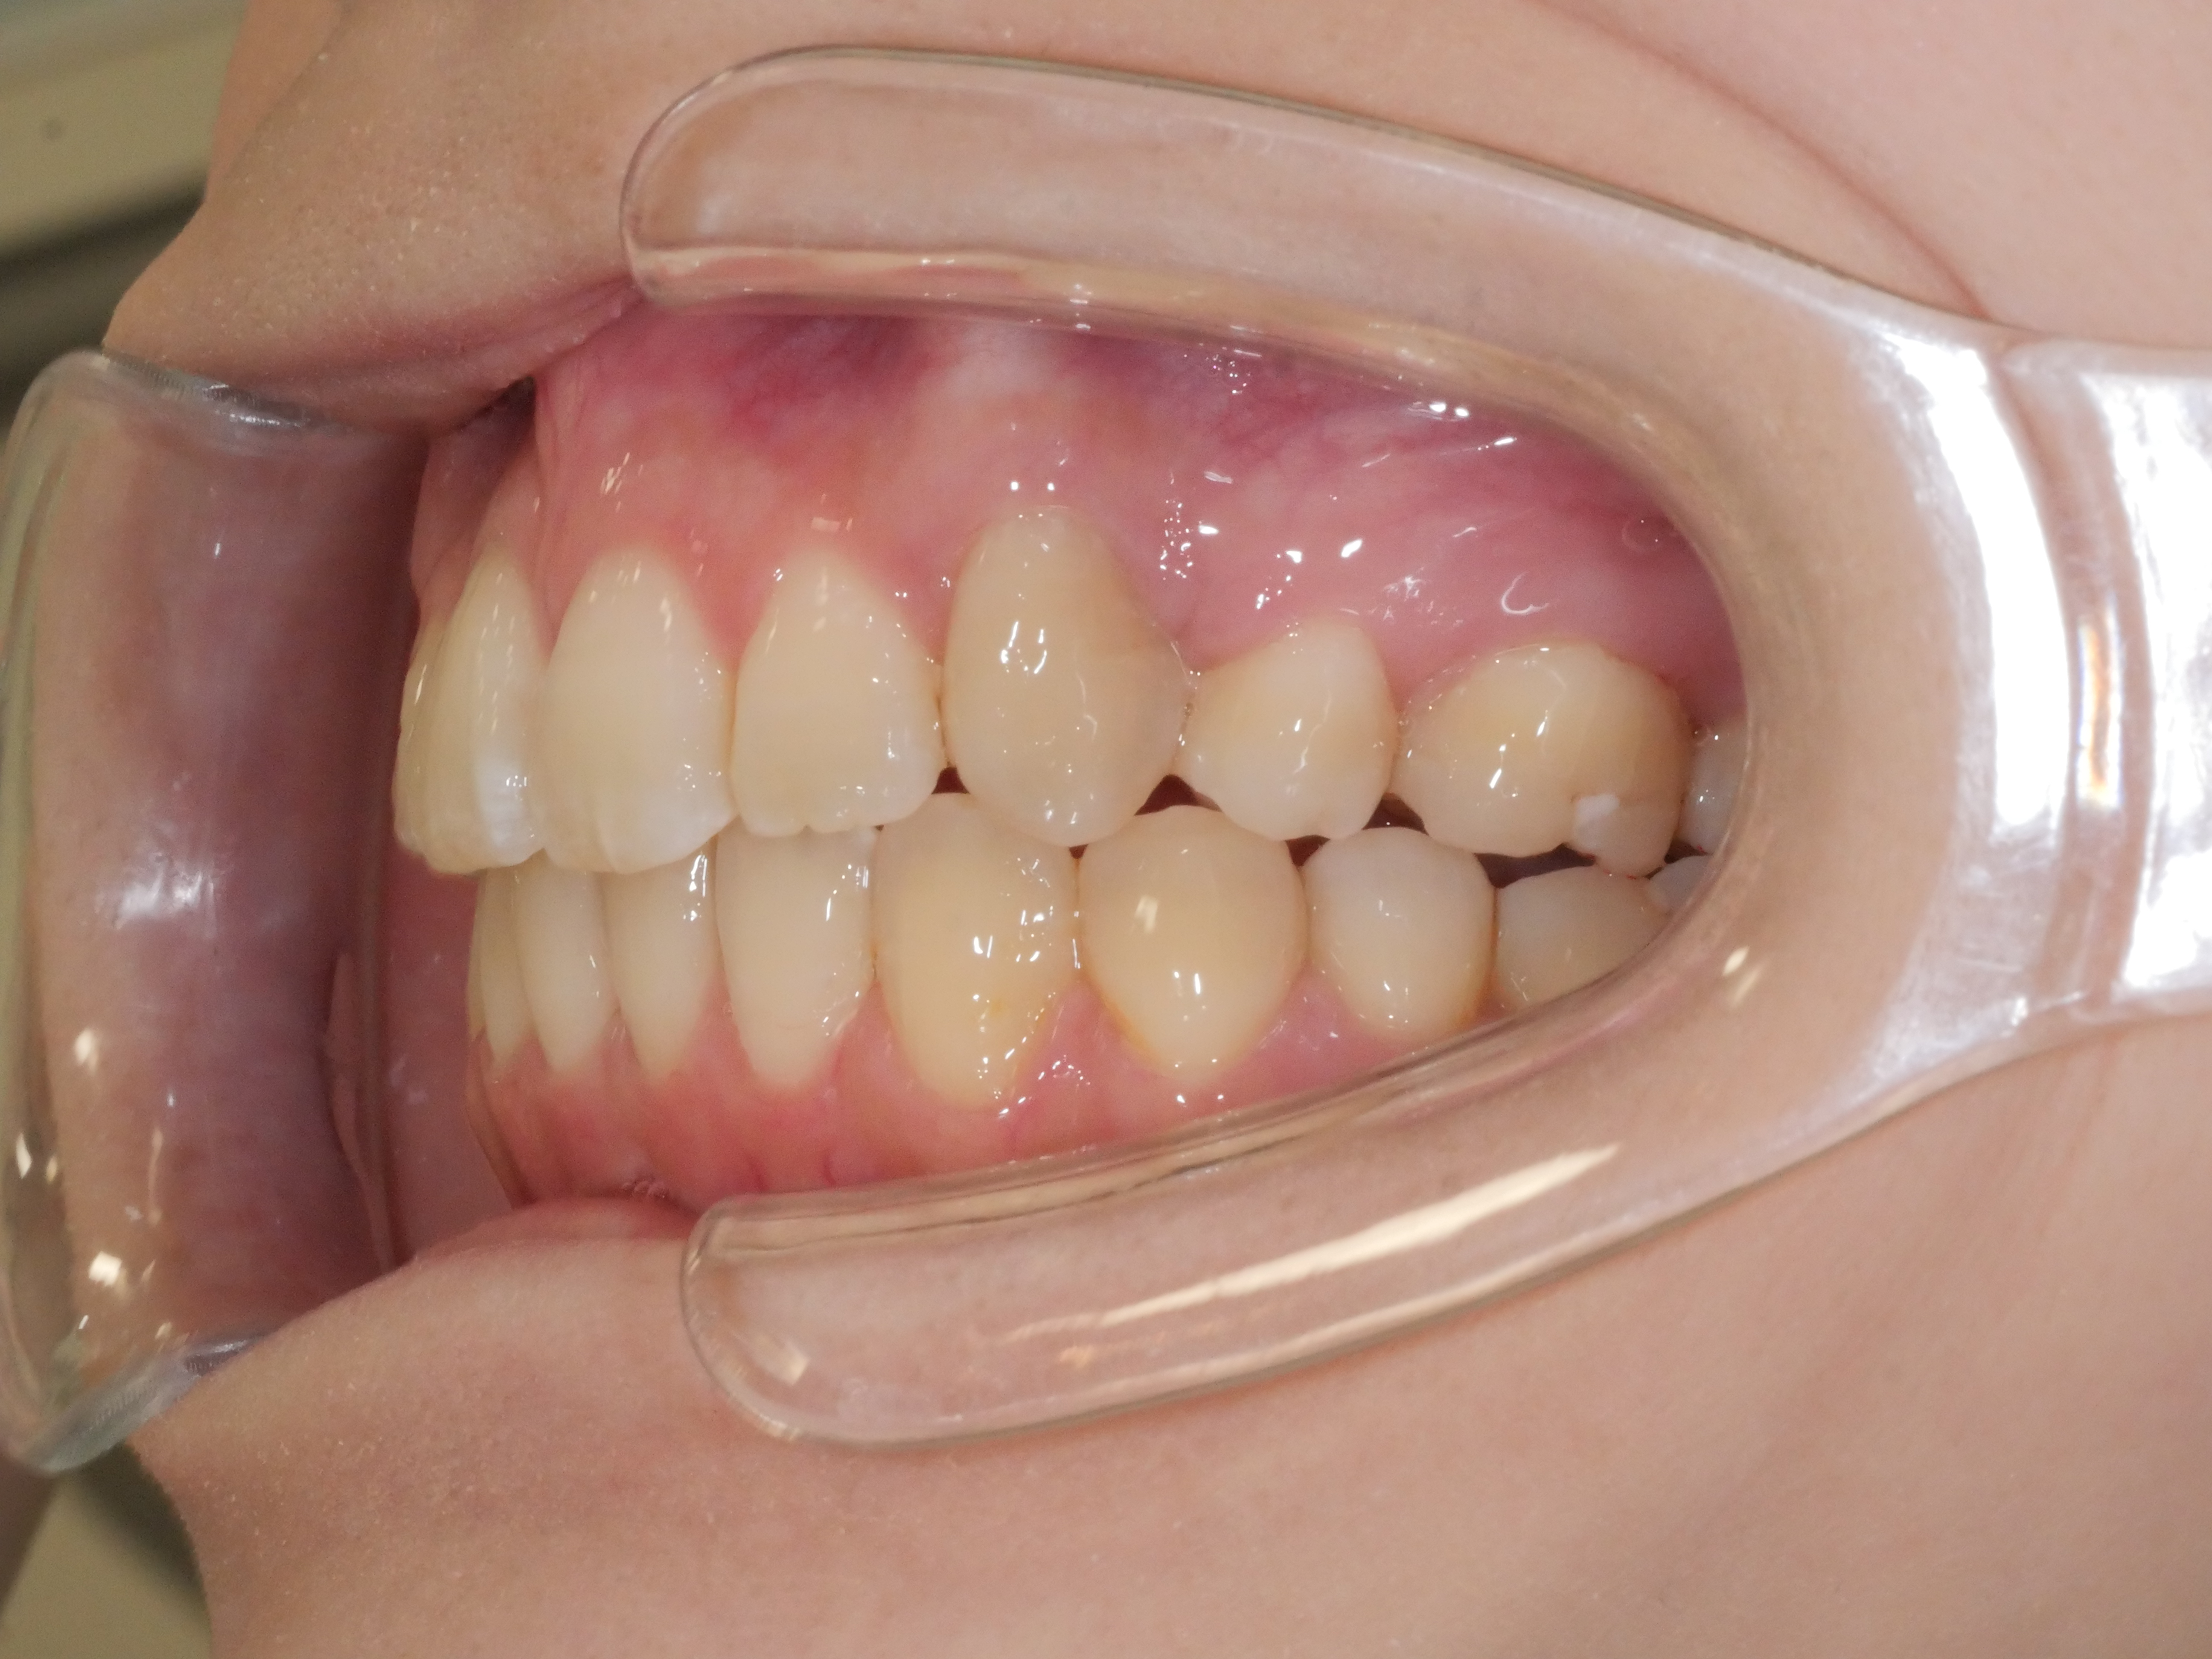

出っ歯を治したい

年齢層 30代

性別 女性

主訴 【主訴】出っ歯を治したい 【診断・症状】上下凸凹、出っ歯(上顎前突)

治療費用 検査・診断:38,500-/裏側矯正治療:1,397,000-(※全て税込)

治療期間 約2年半(33回)

抜歯 有(上4,4、下5,5)

矯正の装置 裏側矯正(舌側矯正)

副作用、リスク 歯肉退縮,歯根吸収,疼痛,咬合の違和感,装置の違和感,虫歯,歯肉炎

case20_出っ歯_before

Before

case20_出っ歯_after

After